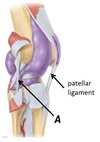

Name ligament A

A - Lateral collateral ligament

Name ligament A

A - Medial collateral ligament

Name ligaments A and B

A - Anterior cruciate ligament

B - Posterior cruciate ligament